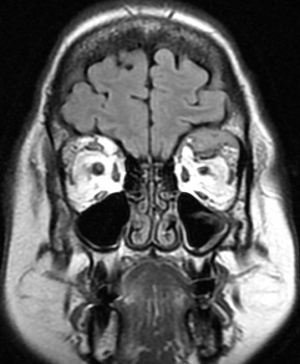

Diagnosis of orbital plasmacytoma can only be made with histopathologic examination of a biopsy of the lesion although classic radiologic features in a patient with or without known multiple myeloma may be suggestive as well. Plasmacytomas are found in the posterior orbit 69% of the time and are extraconal 90% of the time.[6] Most commonly, patients have a superotemporal bony lesion involving the sphenoid or frontal bone with orbital extension causing a mass effect.[6][8] Other radiographic appearances include a lesion infiltrating across anatomical planes including those originating from the sinuses and those emanating from the orbital floor. Bony destruction can be found with these lesions. Additional laboratory tests should be considered in all patients once a diagnosis of plasmacytoma has been established, especially patients without a known history of Multiple Myeloma as a plasmacytoma can be an initial presenting sign.[8] These include tests for anemia, hypoproteinemia, Bence Jones proteinuria, and abnormal proteinemia. Further testing may find hypercalcemia (due to bone destruction), hyperuricemia (resulting from high cell turn over), and elevated ESR. Hypergammaglobulinemia is present in 85% of cases of multiple myeloma.